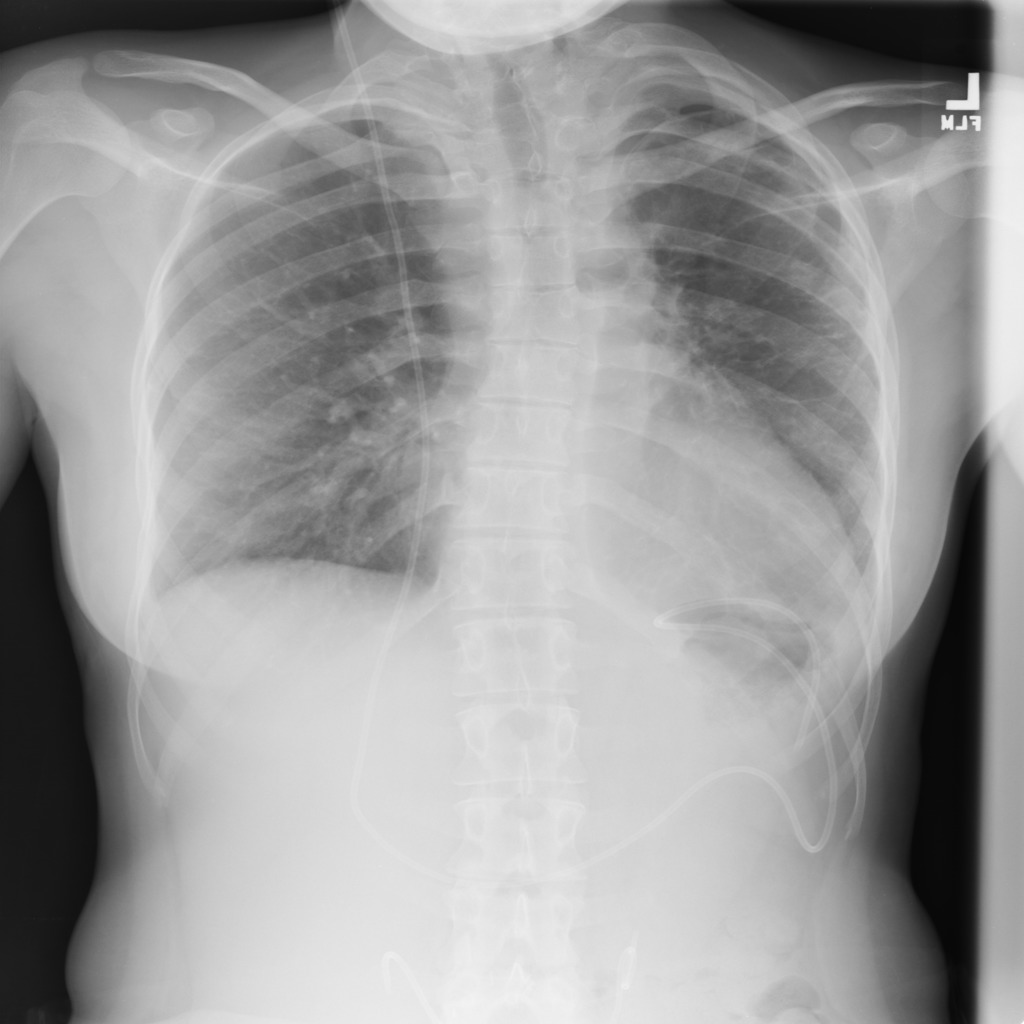

Refer to caption

(a) Image

Figure 2: Segmentation predictions for (a) a random image from test set of SIIM-ACR Pneumothorax produced at each step of our approach: (b) CAM extraction, (c) IRNet, (d) U-Net segmentation, compared to (e) ground truth mask.

We present method’s explainability via disease localization regions; cf. Figure 1. We provide qualitative results of segmentation on validation images from both datasets in Figure 2 and Figure 3. We show the resulting maps at each step of our method; the figures demonstrate how the performance improves after each step. We achieve comparable results to state-of-the-art method on PASCAL VOC 2012; cf. Table 4.